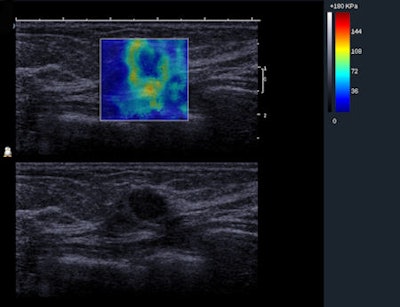

Shear-wave elastography is a technique in which an acoustic pressure wave induces slow-moving lateral waves within the tissue, and the speed of propagation of the shear wave is proportional to the square root of the tissue's elastic modulus. Shear waves travel slower in softer tissue and faster in stiffer tissue. Small changes in velocity occur when the waves pass through tissues of varying stiffness, which is then mapped to create an image. SWE features such as the minimum, mean, and maximum elasticity in a region of interest also can be measured.

In Cosgrove's study, each of the investigators obtained three consecutive SWE images (Aixplorer, SuperSonic Imagine) of 758 masses visible on ultrasound. Of those, 19% were malignant. The reliability of quantitative measurements was assessed by intraclass correlation coefficients. In addition, a blinded observer reviewed images to determine agreement on features for the interobserver reproducibility. Weighted kappa was used to assess the agreement of qualitative elastographic features between observers.

Of the women screened, the average age was 50 and the average mass size was 13 mm. Qualitatively, SWE images were at least reasonably similar for 666 out of 758 (87.9%) masses. Intraclass correlation (ICC) for SWE diameter, area, and perimeter was almost perfect (ICC ≥ 0.94), according to the researchers. Intraobserver reliability for maximum and mean elasticity was almost perfect (ICC = 0.84 and 0.87, respectively). Intraobserver reliability for the ratio of mass-to-fat elasticity was substantial (ICC = 0.77). Interobserver agreement was moderate for SWE homogeneity (κ = 0.57), substantial for qualitative color assessment of maximum elasticity (κ = 0.66), fair for SWE shape (κ = 0.40), fair for B-mode mass margins (κ = 0.38), and moderate for B-mode mass shape (κ = 0.58), orientation (κ = 0.53), and BI-RADS assessment (κ = 0.59).

The heterogeneity of the SWE stiffness was moderately predictive of malignancy in the full set of masses with 70.6% of heterogeneous masses malignant, compared with 4.3% of homogenous masses in a population with 30.8% prevalence of malignancy.

"Consistent image generation is critical for serial studies of masses, for example, follow-up of probably benign masses, or to monitor the response of breast carcinomas to neoadjuvant chemotherapy, and the reliability of SWE could be helpful in these clinical situations," the authors wrote. "Standardizing the color display across elastography systems so that, for example, soft tissues are consistently blue and stiff tissues consistently red, would avoid confusion in centers with multiple different systems, or on receipt of images from outside facilities, and should urgently be addressed."